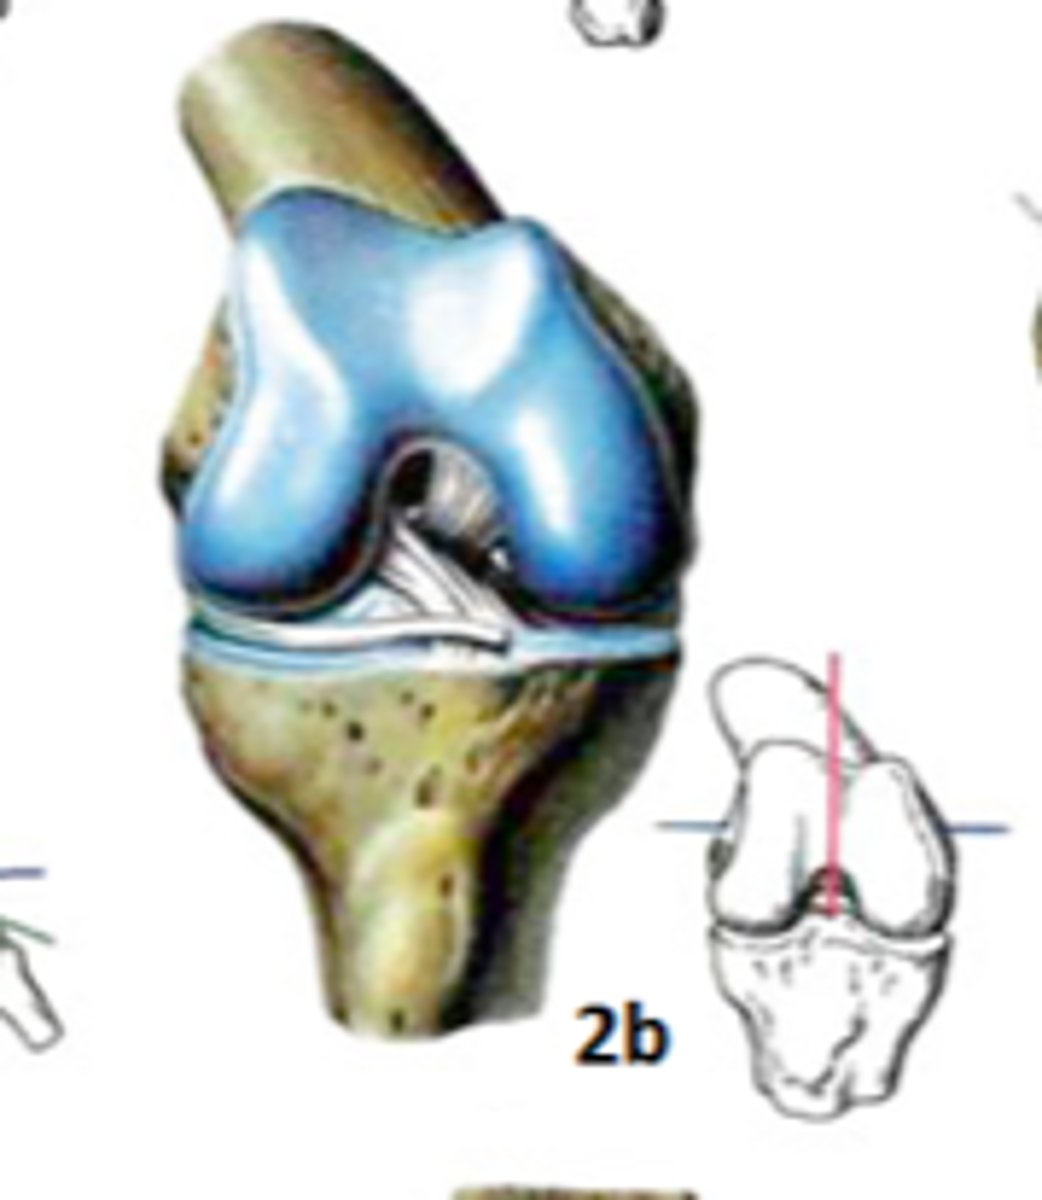

Art. Bicondylaris

Art. genus - ceļa locītava